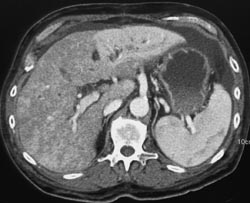

Lipoma of the Liver